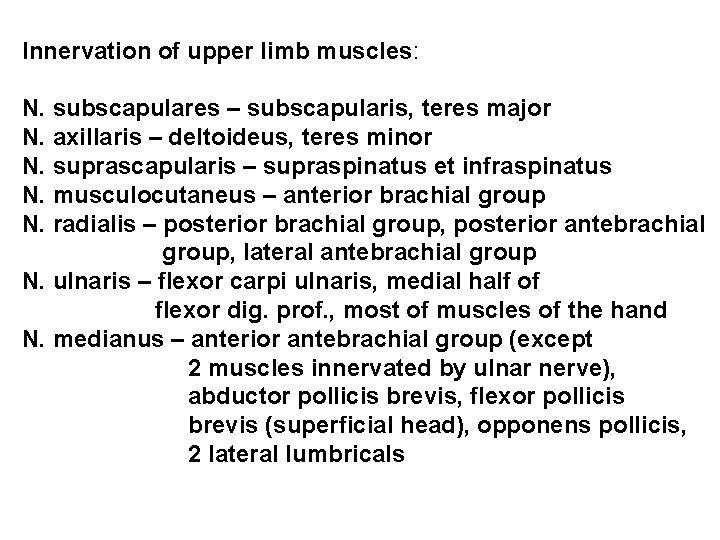

Innervation of upper limb muscles: N. subscapulares – subscapularis, teres major N. axillaris – deltoideus, teres minor N. suprascapularis – supraspinatus et infraspinatus N. musculocutaneus – anterior brachial group N. radialis – posterior brachial group, posterior antebrachial group, lateral antebrachial group N. ulnaris – flexor carpi ulnaris, medial half of flexor dig. prof. , most of muscles of the hand N. medianus – anterior antebrachial group (except 2 muscles innervated by ulnar nerve), abductor pollicis brevis, flexor pollicis brevis (superficial head), opponens pollicis, 2 lateral lumbricals